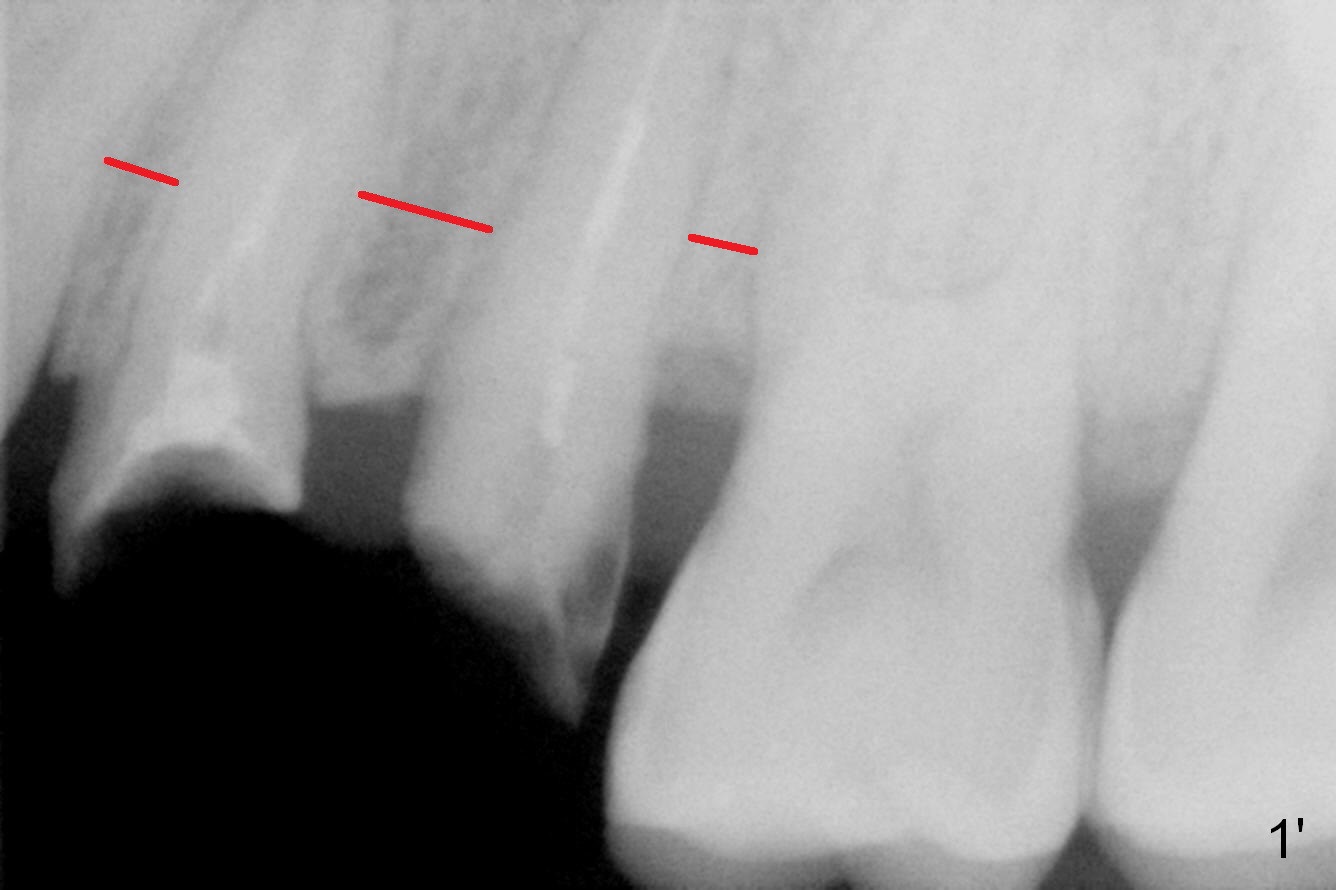

Closer look shows that the width of the interradicular bone is not equal (Fig.1': red line).